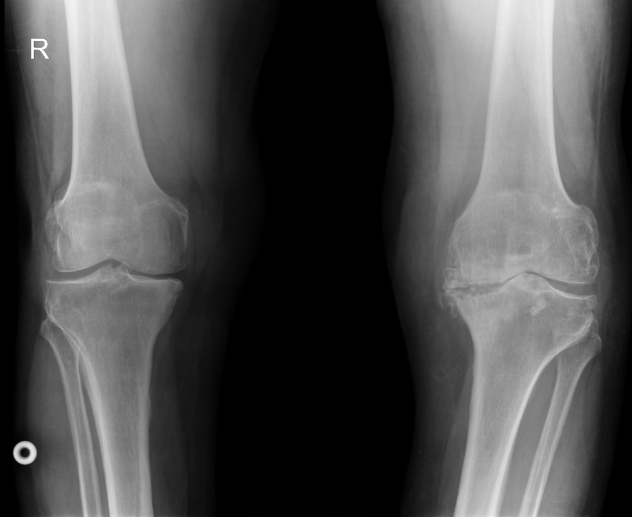

Клинический пример №3.

Правосторонний гонартроз Rg III ст. Смешанная контрактура правого коленного сустава НФ 3 ст. Дефект медиального мыщелка большеберцовой кости. Genu varum.

После тотального цементного эндопротезирования коленного сустава эндопротезом.